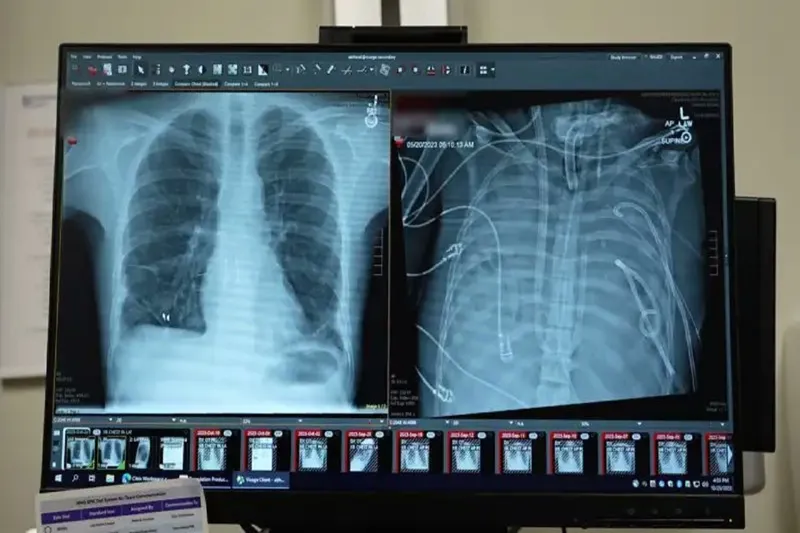

Cerrahlar, akciğerleri geri dönüşü olmayan şekilde hasar gören bir hastayı, organ nakli yapılana kadar yapay akciğer sistemiyle 48 saat boyunca hayatta tutmayı başardı. Yeni sistemin, kalpten geçen kan akışını sürdürürken kana oksijen sağlayabildiği bild

Bunun üzerine cerrahlar, hastanın hastalıklı akciğerlerini tamamen çıkararak geliştirdikleri yapay akciğer sistemine bağladı. Sistem, kalbin sağ tarafından alınan kanı bir pompadan geçirerek oksijen ekliyor ve karbondioksiti uzaklaştırıyor, ardından kanı kalbin sol tarafına yönlendirerek vücuda pompalanmasını sağlıyor. Böylece hem kalbin normal işlevi korunuyor hem de dokulara oksijen ulaştırılıyor.

Daha önce doktorlar, ekstrakorporeal membran oksijenasyonu (ECMO) adı verilen dış destek sistemini kullanarak, nakil bekleyen bazı hastaları akciğersiz olarak hayatta tutmuştu. Ancak Bharat, ECMO’nun kalp için yeterli kan akışını sağlamadığı için gerçek anlamda bir yapay akciğer olmadığını ifade etti.